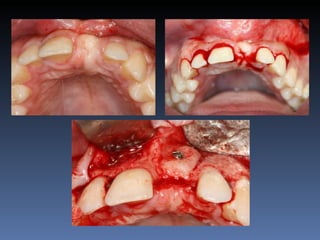

BOX 3

Vanda Alves da Silva

Idade – 51 anos

Sexo – Feminino

Raça – Caucasiana

ASA – II

Data- 26-04-2012

Diagnóstico: Desdentada parcial

Bimaxilar, periodontite 3.1

com mobilidade grau 3.

Plano de tratamento: Exodontia 3.1 , seguida de

instalação de implante com função imediata e

reabilitação provisória fixa.